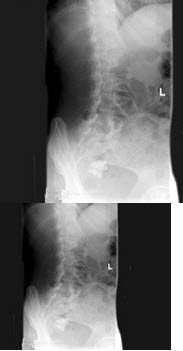

123、单项选择题

女,50岁,因右侧骶髂关节疼痛半年伴左下腹部疼痛,血尿1天,X线检查如图所示,最可能的诊断是()

A.右侧骶髂关节炎

B.右侧致密性骶髂关节炎

C.左侧输尿管下端结石

D.右侧致密性骶髂关节炎;左侧输尿管下端结石

E.以上均不正确